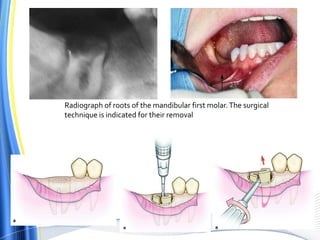

Radiograph of roots of the mandibular first molar.The surgical

technique is indicated for their removal

The surgical technique is indicated for its removal